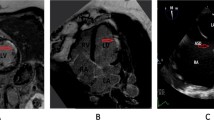

A 65 years old female patient with systolic hypertension, dyslipidemia, history of transient ischemic attack and diagnosis of Patent Foramen Ovale (PFO) subjected to a percutaneous closure procedure with Amplatzer device 1 year ago, was referred to our Hospital for No-ST segment elevation myocardial infarction (NSTEMI). The electrocardiogram ( ECG) showed diffuse repolarization abnormalities (Fig. 7.1), and the peak of high sensible (HS) Troponine T was 0.168 ng/mL. Trans-thoracic echocardiogram revealed a slightly hypertrophic left ventricle (LV), with normal volumes and preserved global and regional function, and Amplatzer device localized in the atrial septum. The contrast echocardiography did not show passage of microbubbles from the right to the left atrium both at rest and after the Valsalva maneuver, rulling out the hypothesis of acute myocardial infarction (AMI) caused by embolization. Coronary angiography did not point out the presence of significant coronary stenosis, while intra-coronary ergonovine administration (up to 50 μg) caused diffuse ST-segment depression at ECG and symptoms, in absence of epicardic coronary spasm (Fig. 7.2, panel A and B). For this reason, the diagnosis of MI and non-obstructive coronary arteries ( MINOCA) due to coronary microvascular spasm (CMS) was done. The medical therapy was optimized with the add of calcium blockers and the patient was discharged without symptoms 7 day after. She remained asymptomatic until 4 years later, when she was admitted at our Hospital for sinus nodal disease and underwent to the procedure of pacemaker implantation.